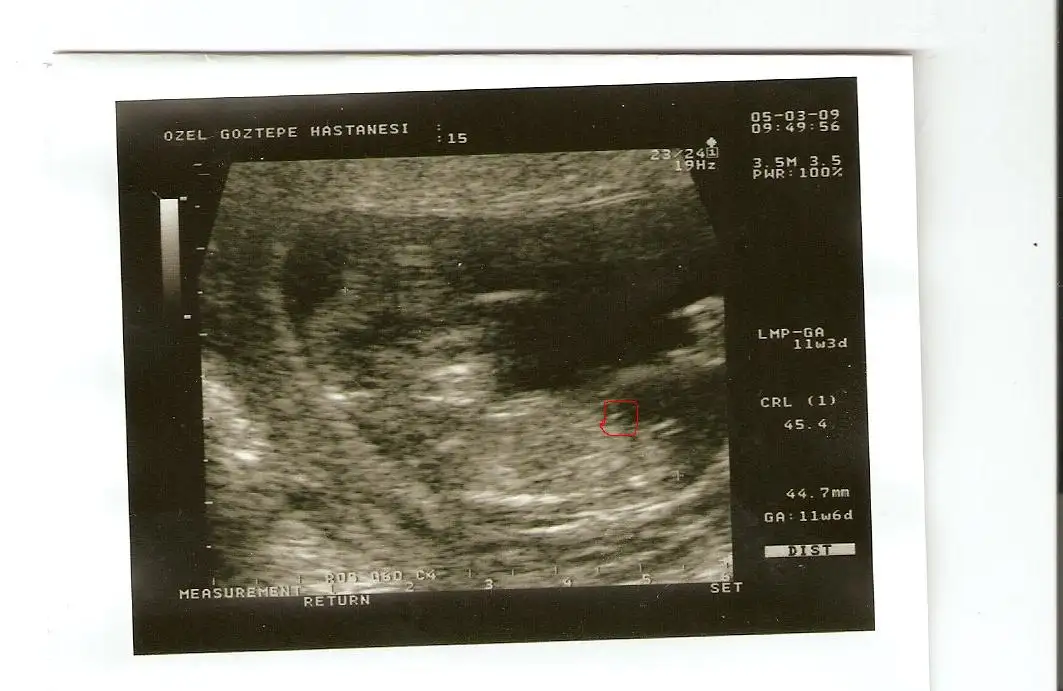

kızlar burda bebişim 11+3 ken.ve bacak arasındaki çıkıntıya bakın:) doktor erkek demişti.